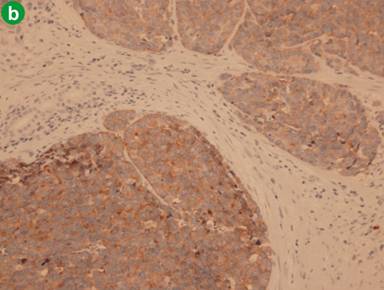

An inclusive narrative review methodology was undertaken. In addition, we briefly review the diagnostic modalities used and the treatment decisions made in the case which presented to our institution. Electronic literature searches were conducted using MEDLINE (PubMed) from 1 January 2000 to 31 August 2011. All English case reports of LCNECs of the ampulla of Vater were selected. The selected search terms and related MESH headings were: “large”, “neuroendocrine” and “ampulla”. In each of the cases selected, the diagnostic criteria for LCNEC of the lung proposed by Travis et al. [12] were satisfied. According to these criteria, tumours are described as having cells at least three times larger than cells of a small cell carcinoma, neuroendocrine morphology (organoid growth pattern, cellular palisading, rosette formation) and an irregular chromatin pattern with brisk mitotic activity [13] (Figure 2a). These criteria were updated in the 1999 WHO classification [14], which added additional criteria including a high mitotic rate of greater than 11 mitoses (when 10 high-power fields of 2 mm2 were examined), extensive necrosis and immunohistochemical evidence of neuroendocrine differentiation. The selected cases also fulfill these additional criteria with all LCNECs in our series immunostaining positive for neuroendocrine markers (Figure 2b). The primary outcome of interest was to determine the overall survival in this rare patient group. The secondary outcome was to determine if having an adenoma in association with a LCNEC improves prognosis.

Figure 2. a. On high power magnification, the neoplastic cells are arranged in well defined solid nest and rosettes with oval vesicular nuclei containing occasional prominent nucleoli. Areas of necrosis are present. b. Tumour cells show strong immunohistochemical detection for synaptophysin. c. Large cell neuroendocrine carcinoma of the ampulla of Vater (top left of field), which is adjacent to a residual villous adenoma of the ampulla with low grade dysplasia (bottom of field). d. Regional lymph node metastasis. Magnifications: 200x, 200x, 20x, and 200x for a., b., c., and d., respectively). |